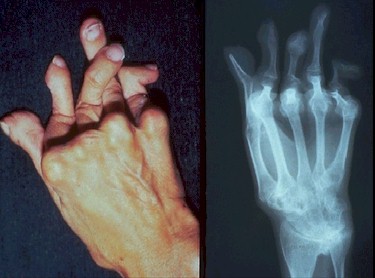

La

artritis Reumatoide es una enfermedad

crónica, potencialmente deformante, que afecta 1% de la

población mundial. Hasta hace pocos años el tratamiento realizado

para detener o retardar la progresión de la enfermedad se basaba en

el uso de medicamentos que habían demostrado eficacia

en la observación

clínica, muchas veces de forma casual.